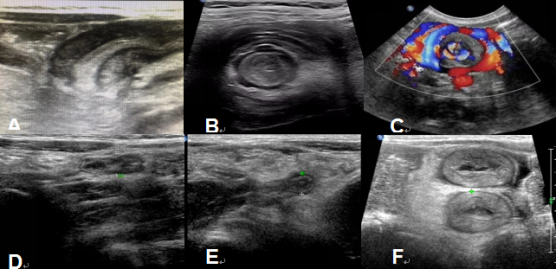

超声特征性征象图:

A:先天性肥厚性幽门狭窄;B:肠套叠;C:先天性肠旋转不良;D:梅克尔憩室;E:阑尾炎;F:腹型紫癜。

超声检查的适应证:肠系膜淋巴结炎、阑尾炎、小肠/结肠炎、肠套叠、肠重复畸形、梅克尔憩室炎、先天性肥厚性幽门狭窄、肠旋转不良伴肠扭转、肠闭锁、腹内疝、新生儿坏死性小肠结肠炎、腹型紫癜等胃肠道疾病。